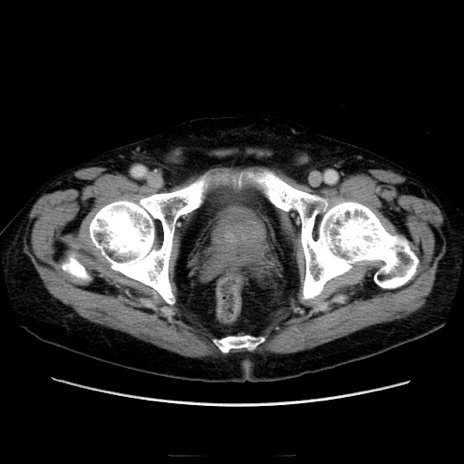

症例21(横断像)

【症例】70歳代男性

【主訴】腹痛

【現病歴】肝硬変・肝細胞癌にてかかりつけの方。約9時間前に食後より腹痛出現。症状が徐々に増悪し、嘔吐出現したため来院。

【既往歴】肝硬変、肝細胞癌(RFA、TACE後)

【身体所見】意識清明、表情苦悶様、BT 36℃、BP 129/78mmHg、P 88bpm、SpO2 97%(RA)、右上腹部から心窩部にかけて圧痛あり、反跳痛なし、筋性防御あり。

【データ】WBC 5800、CRP 0.16